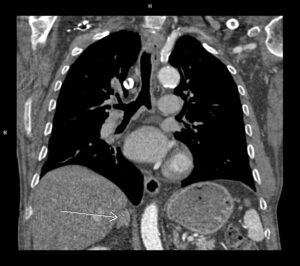

Discuţie caz nr 113: Examinarea angioCT coronariană a fost indicată pentru fenomene de insuficienţă cardiacă și pericardită lichidiană la un pacient cu fibrilație atrială; se remarcă prezența de revărsat lichidian liber pericardic circumferential cu grosime maximă 2 cm în dreptul peretelui liber al ventriculului stâng. Reconstrucția cine evidențiază mișcare paradoxală a septului ce sugerează fiziologie constrictivă.

DE LUAT ACASĂ!!! Calcificările pericardice sunt vizualizate optim cu ajutorul tomografiei computerizate; achiziția angioCT coronariană cu sincronizare ECG evaluează într-o singură investigație: arterele coronare, volumele și funcția ventriculului stâng, poate vizualiza și modificările de cinetică miocardică și caracterizează parenchimul pulmonar, astfel că în pericardită ajută la diagnostic și bilanț etiologic.